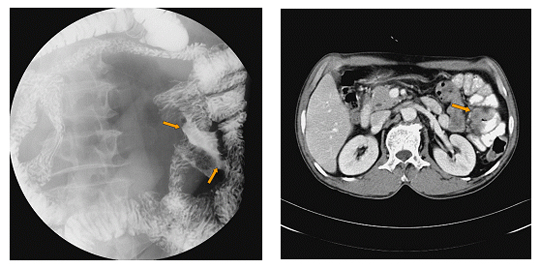

[ 소장(공장)암의 소장조영검사 소견 및 전산화단층촬영 소견 ]

소장조영검사(small bowel series)는 소장의 종양성 병변을 진단하는 방사선학적 검사 중 가장 중요한 검사입니다. 소장조영검사에는 두 가지 방법이 있는데, 경구 소장조영술과 고위 관장법(enteroclysis)입니다.

경구 소장조영술은 조영제(주로 바륨 현탄액)를 마시고 일정한 간격으로 복부 단순 방사선 촬영 사진을 촬영하는 방법으로 일반적으로 소장조영검사라 하면 이 방법을 말합니다. 경구 소장조영술은 50%-80%의 정확도를 보입니다.

고위 관장법은 코를 통해서 십이지장이나 근위부 공장까지 직접 관을 삽입한 후 이 관을 통해 조영제를 소장에 직접 투여하여 단순 방사선 촬영 사진을 촬영하는 방법입니다. 이 방법은 정확도가 90% 내외지만 검사가 힘들고 방사선 조사량도 상대적으로 많습니다.

복부의 전산화단층촬영검사를 통해서 소장 종양의 복강 내 위치를 파악할 수 있습니다. 또한 전산화단층촬영 검사는 종양의 침윤 정도나 간 전이 같은 소장 외 병변의 진단에도 유용합니다. 특히 소장 내 종양이 양성인지 악성인지도 예측할 수 있습니다.